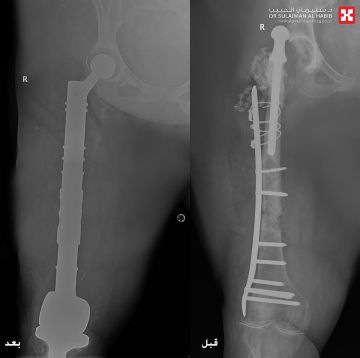

ظلت طريحة الفراش لأكثر من 14 سنة

تمكن مستشفى الدكتور سليمان الحبيب بالخبر، من إعادة القدرة على الحركة والمشي لسيدة ستينية، ظلت طريحة الفراش منذ أكثر من 14 عاماً، بسبب مضاعفات عملية استبدال مفصل الورك الأيمن كانت قد خضعت لها قبل '30' عاماً، وأجرى لها فريق طبي قاده د. عبدالرحمن الرفاعي استشاري جراحة العظام وعظام الأطفال والتشوهات ومفصل الورك المتقدمة، جراحة معقدة وناجحة أنهت معاناتها.

وقال د. 'الرفاعي' الحاصل على الزمالة السويسرية، أن المراجعة جاءت إلى المستشفى بحالة صحية معقدة، إذ أظهرت الفحوصات الدقيقة وجود التهابات حادة ومزمنة وورم التهابي منتشر في مفصل الورك أدى لخروجه، وكذلك في عظمة الفخذ ومفصل الركبة، كما أنها كانت مصابة بمضاعفات عدم الحركة 'تقرحات الفراش' وتصلب المفاصل والظهر، إضافة إلى سوء الحالة الصحية العامة.

وتابع د. 'الرفاعي' قائلاً أن الفريق الطبي وضع خطة علاجية متكاملة مكونة من عدة مراحل، بدأت بإزالة المفصل القديم والورم الالتهابي الذي بلغ وزنه '20' كجم، ووضع أجهزة داخلية تحتوي على مضادات لعلاج الالتهابات، وبعد التخلص منها، جرى استبدال كلي لمفصلي الورك والركبة، وعظمة الفخذ، في تدخل جراحي معقد استمر لـ'5' ساعات، وتكللت جهود الفريق الطبي ولله الحمد بالنجاح التام، حيث نقلت المراجعة بحالة صحية مستقرة إلى غرفة التنويم، وتحسنت حالتها باضطراد مع العناية الطبية الحثيثة، وغادرت المستشفى بعد عدة أيام بحالة صحية ممتازة، ولاحقاً تخلصت من كافة الأعراض التي عانت منها طوال سنوات ما قبل العملية، حيث جاءت إلى المستشفى بعد عدة أسابيع مشياً على قدميها.